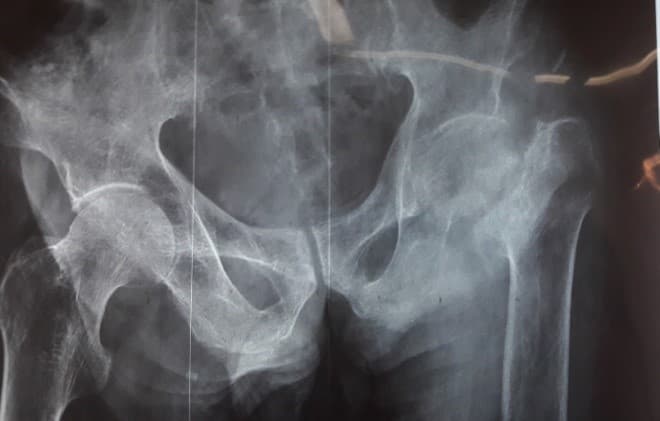

Мэс заслын өмнөх болон дараах рентген зураг

Дунд чөмөгний толгойн үхжил

Тодорхой шалтгааны улмаас дунд чөмөгний толгойд очих цусан хангамж алдагдаж, толгойн хэсэг тэжээлгүй болсноор дунд чөмөгний толгой нь үхжилт бүхий өөрчлөлтөнд ордог түгээмэл эмгэг юм.